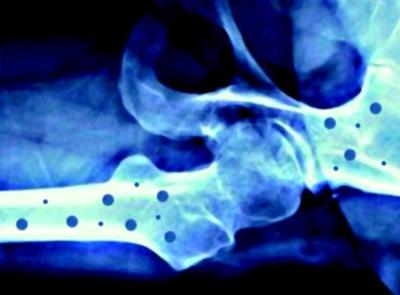

MILANO -"Sono tempi straordinari per l'onco-ematologia. Il futuro delle cure mirate è qui e lo sforzo deve essere quello di vincere la sf...